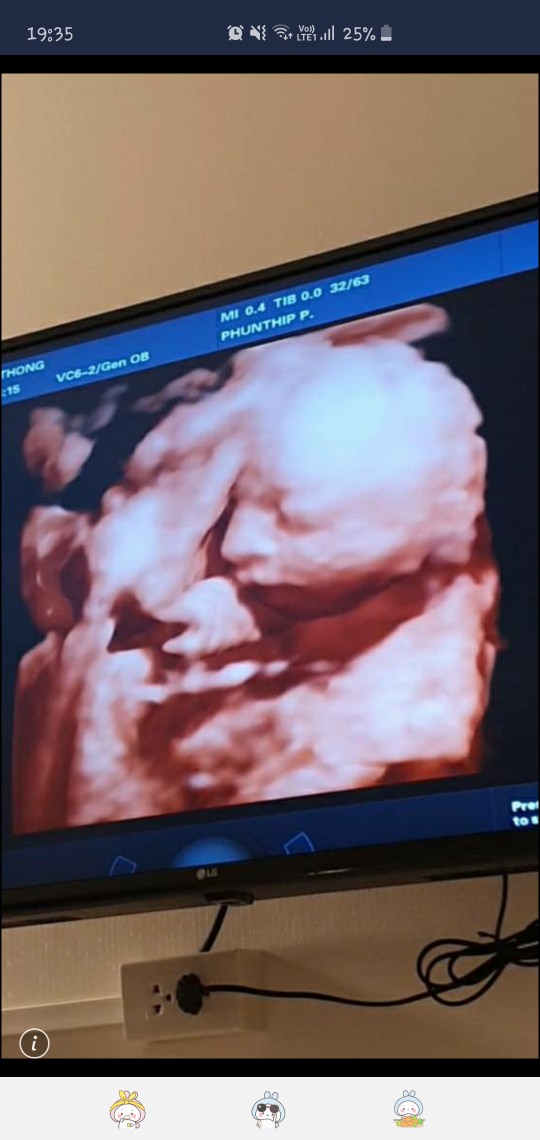

ซาวด์ตอน28วีคค่ะ😊